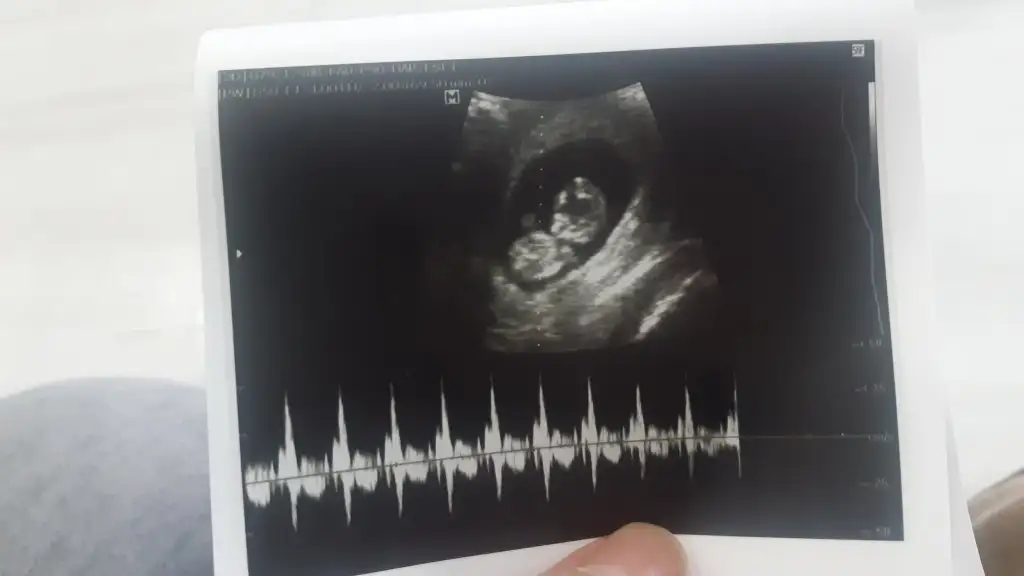

9+5 zamanından ultrason görüntüsü. Karından bakıldı, bana da bakar mısınız rica etsem çok merak ediyorum :)Selam Kızlarbir çok kişi gruplardan beni bilir. Yine yetiştim imdatlara

Çoook uzun bir süre araştırma okuma yaptıktan sonra sizlere bu başlığı açtım çevremde tüm gebelere de denedim. Bunun sırrını çözen İnstagramda (isim vermeyim) işi ticarete dökmüş bile.Nub, Ramzi,Çin Rus Japon Takvimleri, Yüzük Yöntemi bir çok şey size sayabilirim.

5 ve 14. haftaya kadar olan ultrason fotolarınızı paylaşın. Vajinadan mı yoksa karından mı çekildiğini ve kaç haftalık olduğunu da mutlaka belirtin.

Not: Tahmin yaptığım anneler cinsiyet öğrendikten sonra lütfen bana geri dönüş yapın